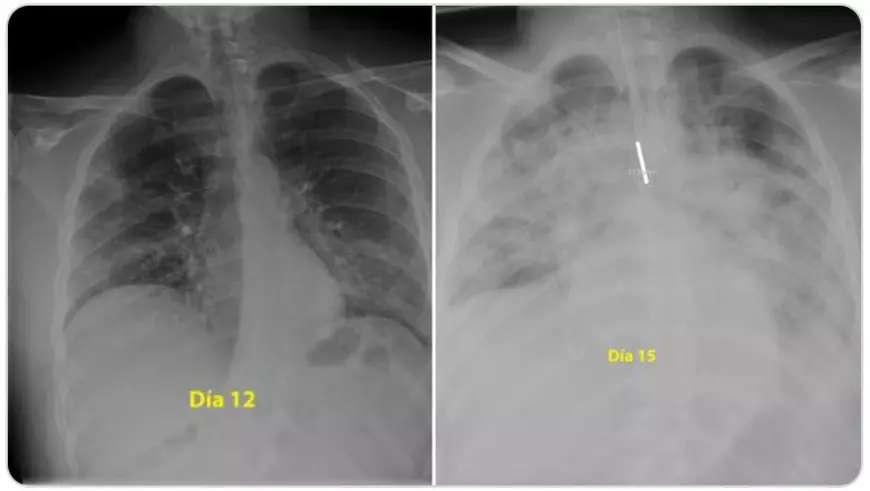

“Pentru cei care cred că sunt nemuritori și continuă să iasă în parc fără să acorde atenție ordinului de a rămâne acasă, acestea sunt radiografiile unui băiat de 28 de ani, intubat la Terapie Intensivă în spitalul meu, pentru #coronavirus. Indiciu: plămânii sunt negri, albul este pneumonie”, a scris medicul pe Twitter. Prima fotografie este în a 12-a zi de boală a tânărului, a doua îi înfățișează plămânii în a 15-a zi de la infectarea cu noul coronavirus, arată Digi24.

Un medic specialist român a confirmat concluziile pneumologului spaniol. Dr. Beatrice Mahler, managerul Institutului de Pneumoftiziologie Marius Nasta din București, a explicat forma gravă a bolii prezentă și în cazul unei persoane tinere.

“E vorba de sindrom de depresie respiratorie acută, este forma severă de pneumonie, care necesită intubație, ventilație mecanică. Din păcate, răspunsul este da, atât de repede și de dramatic li se întâmplă nu numai bătrânilor, ci și tinerilor, tuturor”, a spus Beatrice Mahler, la Digi24.

“Vârsta poate să fie un avantaj în sensul că poate să ajute să depășim acel moment, dacă suntem într-o secție de terapie intensivă, suntem ventilați mecanic, pentru că toate celelalte organe se presupune că sunt sănătoase și pot să susțină momentul critic prin care trece organismul. De aceea, rata de mortalitate este mai mare la cei vârstnici, pentru că boala apare pe un organism bolnav, cu o inimă care are probleme, un ficat bolnav, și atunci depășirea momentului este critică”, a explicat pneumologul.